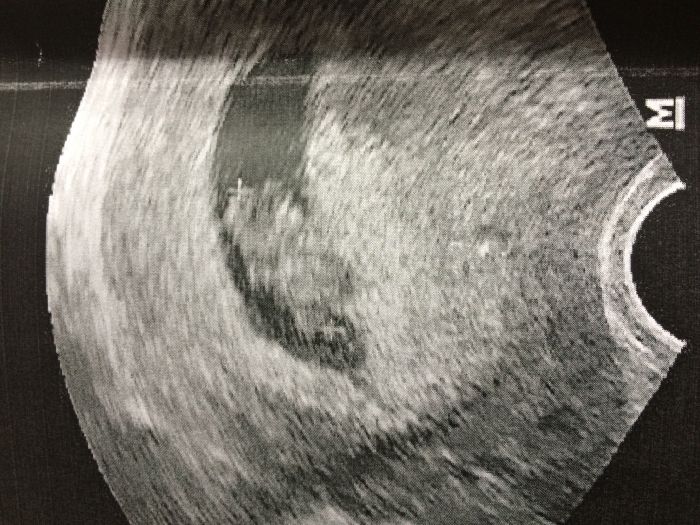

Ahoj holky, tak jsem tu:-)...tak jsem viděla mimi, srdíčko krásně bije, odpovídá velikosti 8+4tt a má už 2 cm! Průkazku ještě nemám, prý raději počkáme do 12 tt, jinak už mám i termín na prvotrimestrální screening, za 14 dní jdu na krev. Teprve mi to všechno dochází! Utz na kterém jsem byla je zastaralý, takže ty fotky neukazuje moc dobře, ale i tak se s vámi musím podělit:-)...a můj dr byl úžasný:-)

Jé Tulipánko :-) první fotka :-) Vašeho mimi :-)